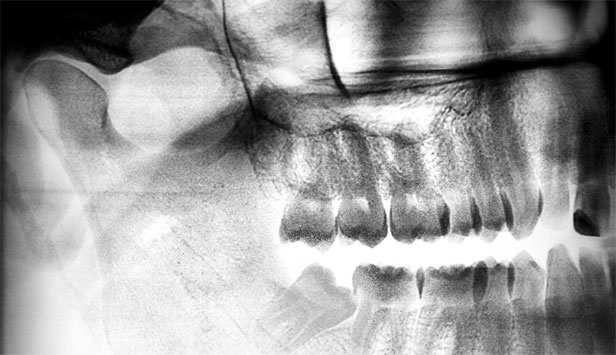

Иллюстрация к книге — Злые зубы [i_032.jpg]

А на этом снимке наглядно видно, как «восьмерки» повреждают «семерки». Зачастую при такой ситуации уже глубокий кариес корня седьмых зубов и их приходится удалять вместе, так как, к сожалению, уже не спасти.

Не надо тянуть и дожидаться, когда зубы мудрости нанесут вред. Сделайте снимки всех зачатков восьмых зубов, и, если они расположены криво, есть смысл удалить их до окончательного формирования корневой системы.